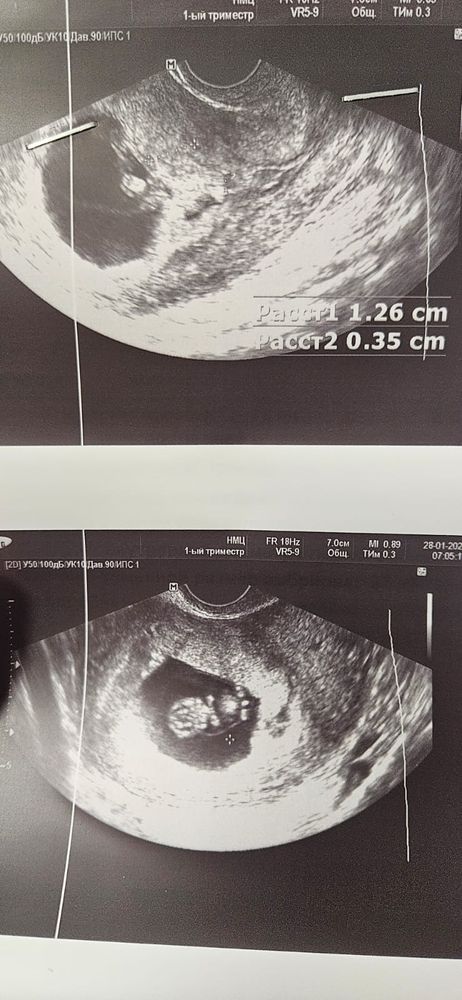

УЗИ 9,6 недель и много вопросов

Всё о нашей беременностиКрайний раз узи было в 9 недель. сегодня поехала ,т.к. снова был приступ панички. тревога, самочувствие и как вишенка на торте - ужасный сон...

КТР в 9 недель - 21мм

КТР 9.6 - 23,9мм

ПЯ в 9 недель - 43мм

ПЯ в 9.6 - 37мм (оно было сплющено из-за тонуса, возможно поэтому не верно было замерено, допускаю)

ЧСС 157 , так же как и в 9 недель.

по КТР идет отставание на неделю ровно, врач сказала не переживать. все норм. так ли это?

Тонус ушел. Но появилось краевое предлежание. Сказала возможно поднимется еще.

Но самое интересное, что в прошлый раз она написала прикрепление по задней стенке. сейчас указала что по передней, это как?)